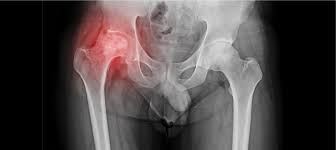

Hip pain can severely affect mobility, daily activities, and quality of life. Conditions such as osteoarthritis, avascular necrosis (AVN), fractures, and post-traumatic arthritis often require surgical intervention when conservative treatments fail. The Quick Recovery Hip Surgery in Harda ensures patients regain independence and mobility in the shortest time possible. Modern surgical techniques, structured rehabilitation, and expert care allow patients to return to daily activities safely and efficiently.

Quick recovery hip surgery addresses conditions that severely limit mobility and quality of life. Severe osteoarthritis, avascular necrosis (AVN), post-traumatic arthritis, fractures, and chronic hip pain unresponsive to medications or physiotherapy are treated using advanced surgical techniques.